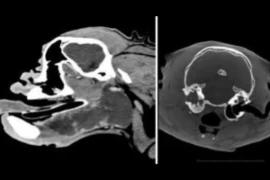

Sichtbar - der praxisorientierte Röntgenkurs nach Leitsymptomen

Ganz nach dem Motto: “Man sieht nur, was man kennt” werden in diesem Kurs in 5 on-demand Webinaren Röntgenbilder nach Leitsymptomen besprochen. Ziel ist es, die Anzahl an sichtbaren Informationen pro Aufnahme zu erhöhen.Referenten:Innen Kristina Lederer, Penelope Baloi, Beate Katharina Bosch -